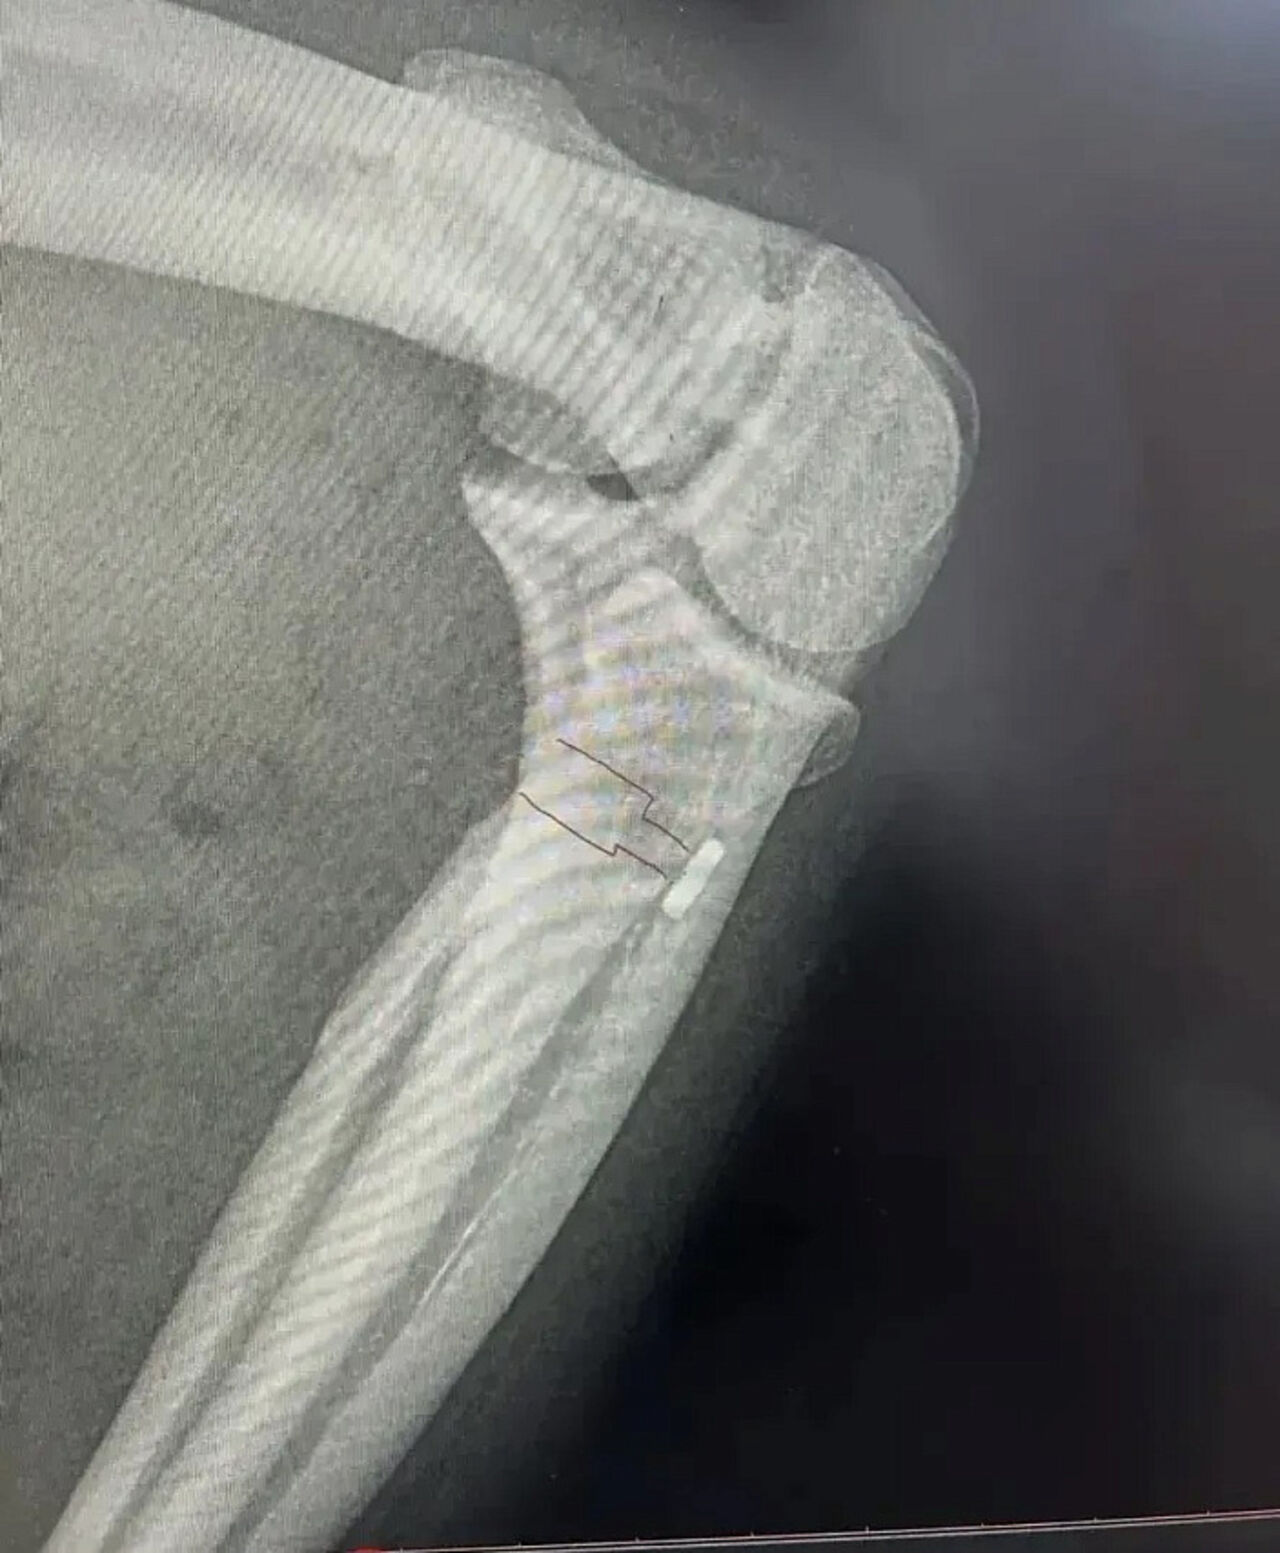

При диагностике врачи увидели давний разрыв сухожилия бицепса. Со временем родное сухожилие ссохлось и потеряло целостность – пришить его уже нельзя.

Травматолог-ортопед Начын Монгуш предложил другой путь. Вместо утраченного сухожилия хирург использовал ткань самого пациента – взял сухожилие длинной малоберцовой мышцы голени. Этот кусок почти не влияет на походку и равновесие, зато по прочности не уступает родным связкам.

Операция прошла успешно. Врач воссоздал правильное крепление бицепса к кости, вернул мышце способность эффективно сгибать руку в локте.